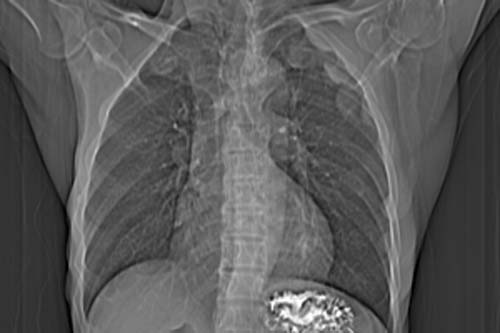

患者,男,65岁,咳嗽,胸痛

胸膜下见多个软组织结节且以宽基底与胸膜相连,上部肋骨似见骨质破坏,考虑:恶性胸膜间皮瘤。

影像表现不再赘述,支持周围型肺癌,伴胸膜转移。排除胸膜原发肿瘤。

说肺癌纵隔窗上不典型,而胸膜间皮瘤却又没胸水。我觉得胸膜间皮瘤放第一位。

左肺下叶周围型肺癌合并左侧胸膜转移

ct所见;左下肺可见片状阴影,密度不均,边缘尚清晰,胸膜方向见有条索相连,纵隔窗未见具体结节。左侧胸膜下见多个软组织结节且以宽基底与胸膜相连,右侧胸锁关节层面亦见软组织结节广基与胸膜相连。纵隔未见肿大淋巴结,气管,支气管开口正常。

影象;1,左下肺感染性病变,结核可能性大。

理由:肺窗显示片影,纵隔窗未能显示具体结节,说明渗出成分为主。建议必要时薄层扫描观察。

2,胸膜病变,以胸膜间皮瘤可能性大。

左肺下叶基底段见结节样稍高密度影,内密度不均匀,边缘不清,可见索条影与邻近胸膜粘连,左侧胸膜上见多个结节影,以宽基底与胸膜粘连.纵隔不宽,内未见明确肿大的淋巴结.

考虑:周围型肺ca伴左侧胸膜转移可能性大 ,不完全除外左肺下叶炎性假瘤,左侧胸膜间皮瘤可能,建议强化ct扫描。

ct所见:左肺上、下叶近胸膜肺外带可见多个大小不等的结节灶,边界清楚,边缘比较光整。近胸膜病灶似与胸膜以宽基底紧连。提供的病史比较简单,我考虑:1、胸膜原发肿瘤可能性大(就形态来看恶性可能性不大);那么大胆的设想一下,左下叶结节是否与它有必然的联系呢?也可以是结核或周围型肺癌。2、还可以考虑为胸膜和肺内的都是转移灶,病人65岁,是不是其他部位的恶性肿瘤转移过来的呢?因为病灶比较表浅,但一侧发病较少见。3、周围型肺癌并胸膜转移的可能性比较小,一是肺内病灶较小,单发,胸膜结节相对较多,位置较远,临近胸膜无受侵。